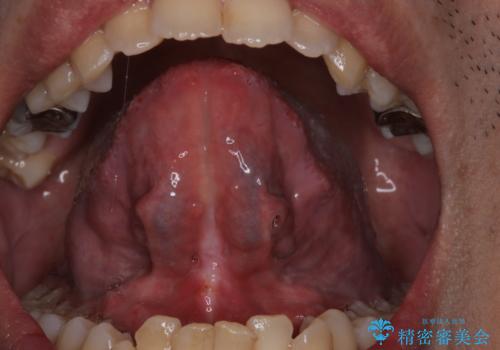

[ 舌小帯の形成術 ] 短い舌の改善をしたい

担当医 大元洋佑

![[ 舌小帯の形成術 ] 短い舌の改善をしたいの症例 治療前](https://seimitsushinbi.jp/wp/wp-content/uploads/2024/01/a2134e91acf88c355613990e1bd96304-500x350.jpg?v=1706348748)

![[ 舌小帯の形成術 ] 短い舌の改善をしたいの症例 治療後](https://seimitsushinbi.jp/wp/wp-content/uploads/2024/01/52db9b03a5d3a93572f61dbac2597f07-500x350.jpg?v=1706348765)